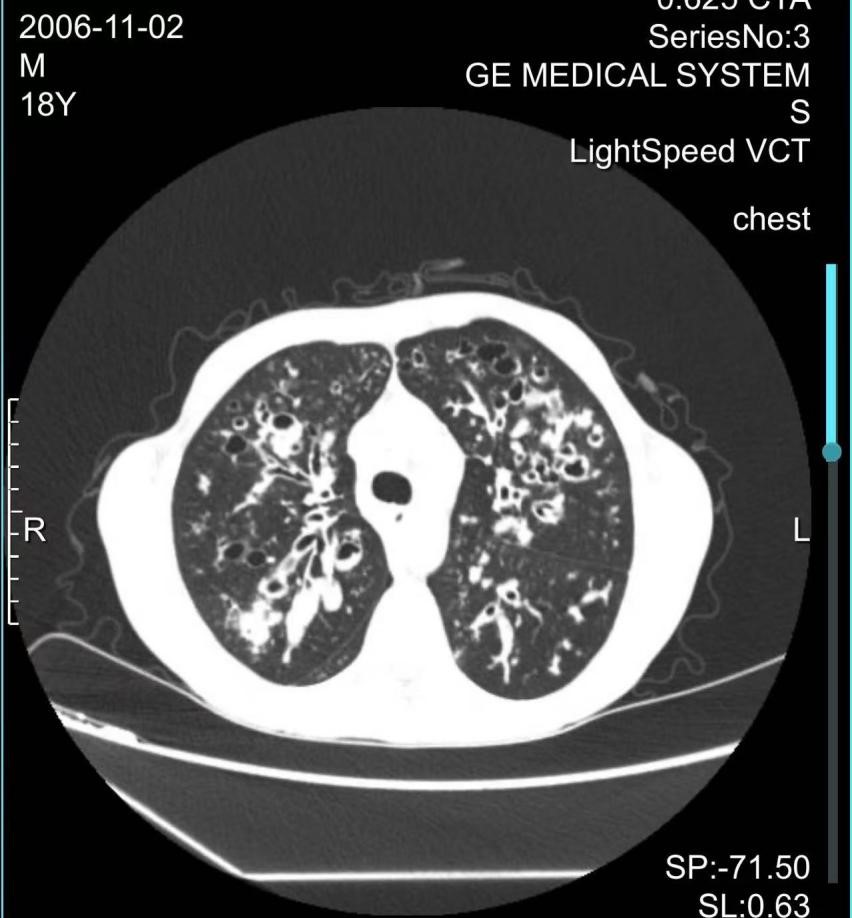

首例患者为2岁患儿小宇(化名),多次重症肺部感染伴胃食管反流,导致肺部炎症迁延不愈。经噬菌体雾化治疗72小时后,痰培养转阴,感染得到完全控制。第二例为18岁患罕见病囊性纤维化的小金(化名),多次因重症肺炎、呼吸道感染至多家医院治疗,本次在上海市儿童医院确诊为肺部多重耐药铜绿假单胞菌感染,在药物治疗重重受阻的情况下,通过支气管镜注入噬菌体,成功开展肺囊性纤维化合并多重耐药铜绿假单胞菌感染的重症患者噬菌体治疗,为患者后续进一步治疗带来希望。

头图为患儿肺囊性纤维化伴感染的CT影像。院方供图